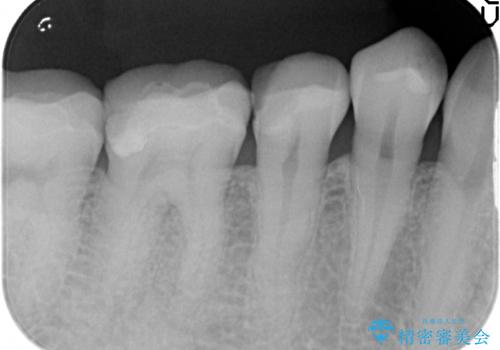

- 右下でものを咬むと痛むので診て欲しいといらっしゃった方の症例です。

検査の結果右下5番目の歯の神経が死んでいたため、根管治療を行った後、オールセラミッククラウンによる補綴を行いました。